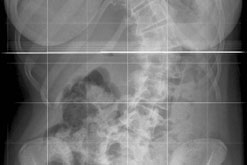

X-Ray

Curvature of the spine that predominantly affects girls.